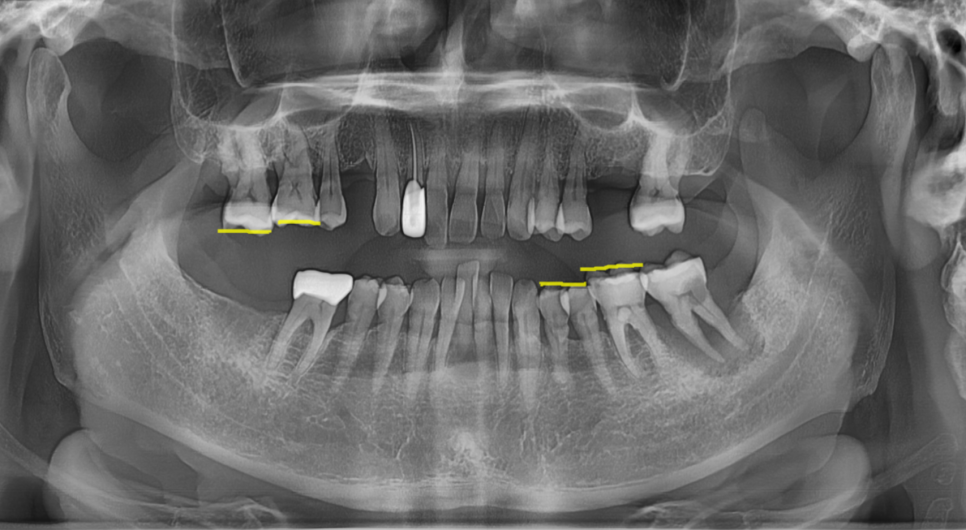

250702 치아 높이 차이를 확인해보세요

그리고 그땐 이렇게 말씀하세요.

“처음엔 하나였는데… 이게 왜 이렇게 커졌죠?”

“처음엔 간단한 문제였는데...”

“결국 수백만 원 들어가는 치료로 이어졌어요...”

이런 사례, 너무 흔합니다.

정말로요...